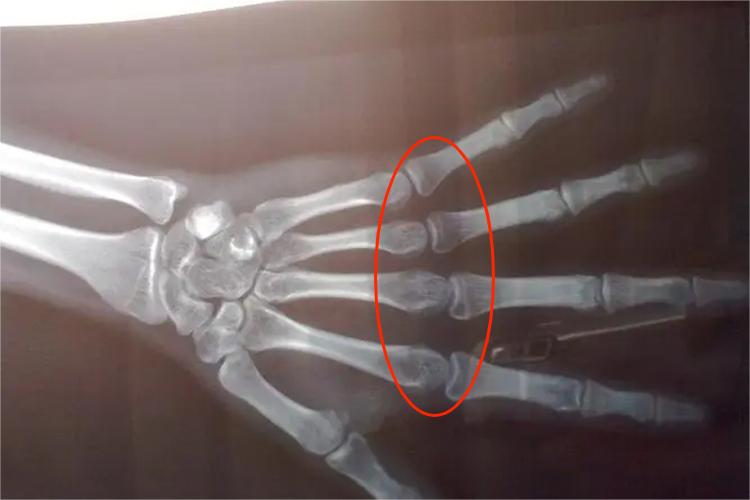

骨骺线闭合在X光线片上可清楚地观察到,一般使用左手后前位手腕骨X线片。骨骺板与骨骺线在X线片上表现为干骺端与骨骺间的软骨投影,在儿童时期骨骺板呈透明带,随着年龄的增大逐渐变窄呈透亮线,即骨骺线,直至完全消失,表示骨骺线闭合。

骨骺线是否闭合的检查常见于手腕骨骨龄分期法,即根据X线片手腕骨发育情况,评价个体生长发育的方法。当X线片见骨骺线闭合时,即表示生长发育终止,正常情况下女性为14岁,男性为16岁。